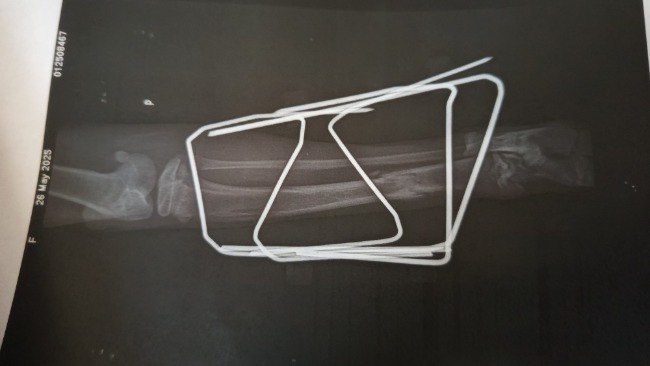

Roksi Koty

Pętla ma nowy dom 🥹🥹 To wszystko nasza i Wasza zasługa ❤️ Bez tych wpłat nie mielibyśmy sami szansy jej uratować, a ona nie miałaby szansy na życia jakie teraz ma. A zdecydowanie zasługuje na to najlepsze, jej wola walki na zawsze pozostanie w mojej pamięci 🥹